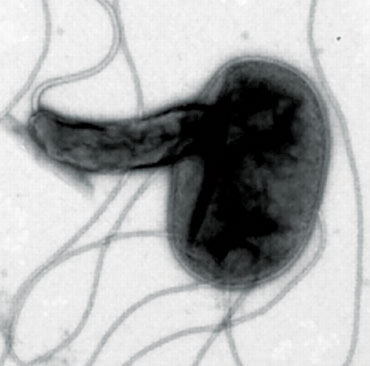

BACTERIAL COMBATANTS Bdellovibrio bacteria (yellow) attack larger bacteria (blue), using the prey’s remains to replicate. Bdellovibrio microbes are a kind of living antibiotic.

The notion of predatory bacteria sounds a bit scary, especially when Kadouri likens the most thoroughly studied of the predators, Bdellovibrio bacteriovorus, to the vicious space creatures in the Alien movies.

When it encounters a gram-negative bacterium, the predator appears to latch on with grappling hook–like appendages. Then, like a classic cat burglar cutting a hole in glass, B. bacteriovorus forces its way through the outer membrane and seems to seal the hole behind it. Once within the space between the outer and inner membranes, the predator secretes enzymes — as damaging as the movie aliens’ acid spit — that chew its prey’s nutrients and DNA into bite-sized pieces.

B. bacteriovorus then uses the broken-down genetic building blocks to make its own DNA and begin replicating. The invader and its progeny eventually emerge from the shell of the prey in a way reminiscent of a cinematic chest-bursting scene.